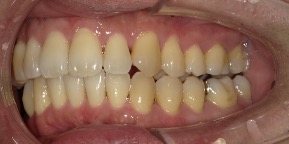

29歳女性のビフォーアフター

| 診断 | 叢生(デコボコがある状態)、過蓋咬合 |

| 治療方針 | インビザラインシステムにて主にIPR(歯と歯の間をわずかに削合してスペースを獲得する方法)を組み込んだ動的矯正治療を行い、叢生を改善後、保定を行う。臼歯部の咬合関係はプランの関係上維持して叢生と前歯部の咬合改善を目指した。 |

| 治療費 ※ | 60万4千円(診断、型取り、PMTC、保定装置を含む料金) |

| 治療期間 | 1年5か月 |

| リスク | 1日20時間以上マウスピースを使用できない場合、歯が動かない可能性がある。装着時や食事時に痛みを伴う。歯肉退縮や虫歯になるおそれがある。また、指導通りに装着できていない場合や適切なブラッシングが出来ていないとそのリスクが高くなる。歯根が短くなることがある。ごくまれに歯の神経が損傷してしまうことがある。過去にぶつけたり深い虫歯治療をしたことがあるとそのリスクはやや高くなる。矯正後には保定装置が必要。適切な使用ができない場合、後戻りの原因となる。将来的に歯並びが動いて再矯正が必要な場合がある。親知らずが正常に生えていない場合、その可能性がやや高くなる。 |